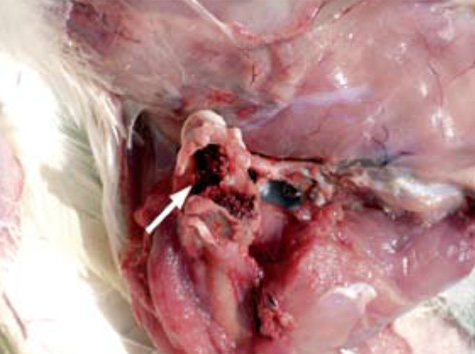

2.- La prevalencia observada de FHN, en asociación con osteomielitis, ha sido considerada por un gran número de investigadores como una de las principales causas de cojera en pollos de engorde comerciales. A menudo, en la autopsia, la cabeza del fémur fracturado está separada del fémur, y permanece en el acetábulo (flecha) en un intento de separación de los huesos.

3.- Sobre la base de los datos que se han recolectado en los pollos de engorde, E. coli podría tener un papel primordial en la etiología de la osteomielitis y FHN a diferencia de lo encontrado en reproductores de pollos de engorde en crecimiento donde participó principalmente S. aureus. Necrosis (flecha) y pérdida de la parte metafisaria del fémur (f) en la osteomielitis.